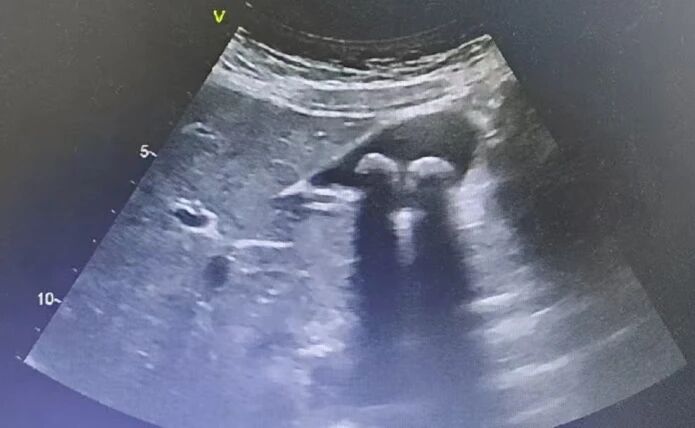

胆囊结石超声影像

1.胆囊结石/胆囊炎:超声能清晰显示结石,并观察胆囊壁是否增厚、周围有无积液。